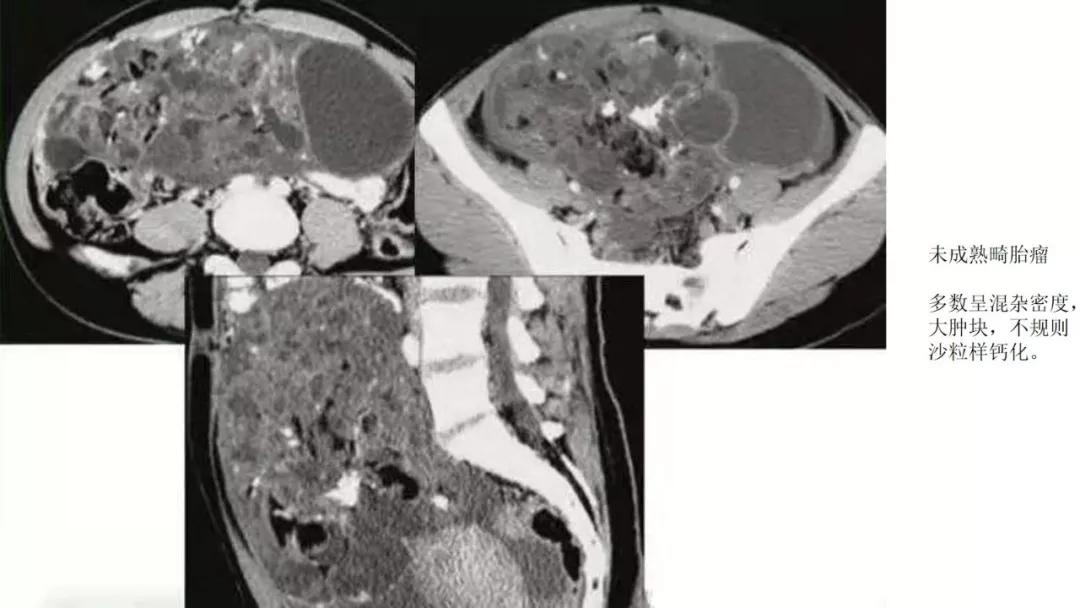

恶性者常呈实性或混杂性肿块,多数边界清楚,可伴有不规则沙粒状钙化。无性细胞瘤常为实性肿块,轻度强化,内胚窦瘤实性成分明显强化,不成熟畸胎瘤呈混杂密度。结合年龄及临床生化检查,有助于诊断。